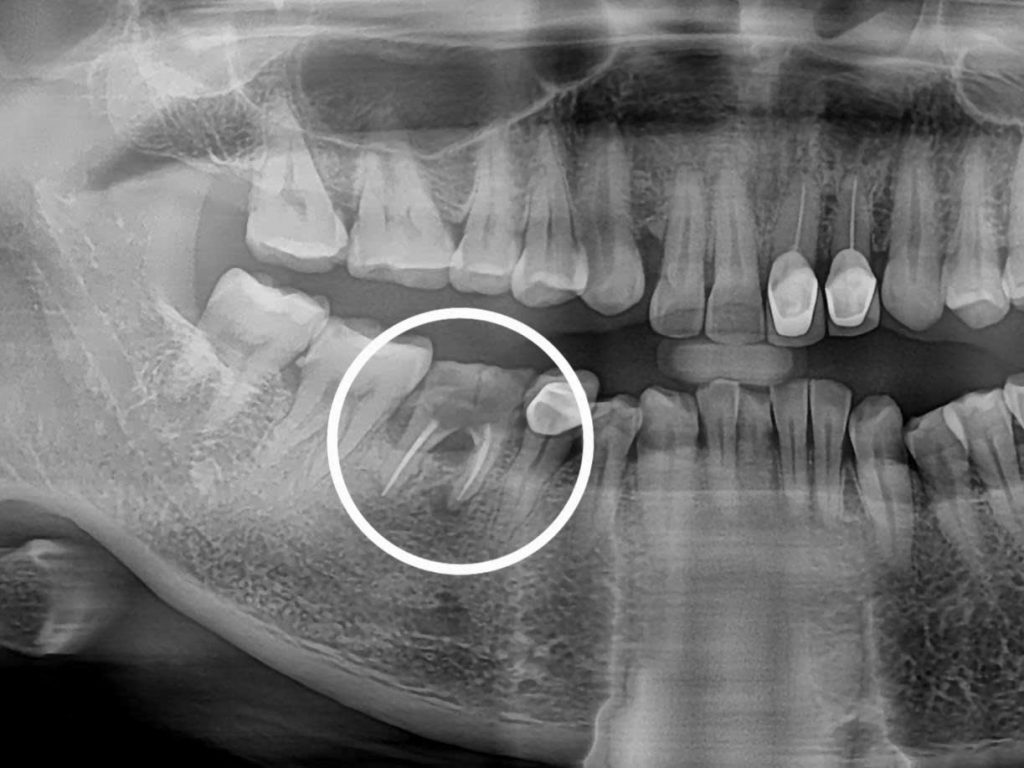

Hệ Thống Chẩn Đoán CT Conebeam 3D

X-Quang 3D giúp lập kế hoạch giả định cá nhân hóa, tối ưu hóa độ chính xác và kiểm soát rủi ro phẫu thuật.

Cùng tìm hiểu quy trình cấy ghép Implant an toàn tại Nha Khoa Ace Smile qua trải nghiệm thực tế của anh Cường.

Bước 1 – Thăm Khám & Chụp XQ 3D